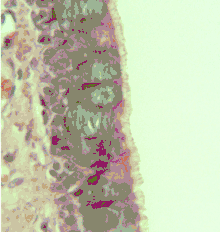

Cross-section of pseudostratified columnar epithelium

Second cross-section